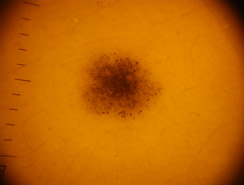

Dermatoscopia

Lo studio e la diagnosi delle neoformazioni cutanee attraverso strumenti specifici indicati per un'analisi delle caratteristiche strutturali superficiali e profonde delle varie neoformazioni cutanee: dermatoscopia, dermalite a luci fotocromatiche, mappatura nevica con videodermatoscopia digitale.

Al fine di una corretta diagnosi dei nevi, e dunque di un'efficace prevenzione da forme tumorali, è indispensabile visionare in profondità i caratteri di ogni formazione nevica. Ciò è reso possibile dall'utilizzo del dermatoscopio e dalla concomitante mappatura nevica, con l' eventuale rimozione chirurgica o laser di: